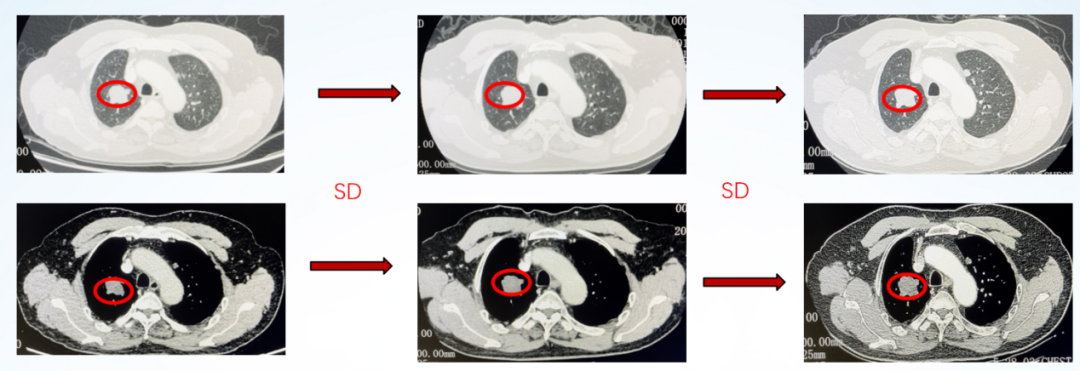

患者化疗后消化道反应重,自觉不能耐受,拒绝继续静脉化疗及静脉靶向药物治疗。与患者沟通病情后更换治疗方案,进入三线治疗,2020-5上旬开始口服呋喹替尼 5mg qd 。疗效评价SD。

影像学评估:

图6、呋喹替尼单药治疗期间,影像学评估持续SD:第1排(2020-05)、第2排(2020-07)、第3排(2020-09)、第4排(2020-11)